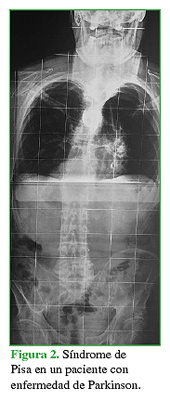

Se han descrito múltiples alteraciones espinales principalmente relacionadas con trastornos del equilibrio tanto en el plano coronal como en el sagital (Figuras 1,2,3).

En este tipo de pacientes, las deformidades posturales asociadas están relacionadas con el aumento del tono de los músculos axiales y de las extremidades acompañado de la disminución progresiva de la propiocepción neuronal.3,4 El 3-12,9% tiene camptocormia, se trata de una postura anormal con una marcada flexión de la columna toracolumbar que se incrementa con el tiempo y la fatiga durante el día y al caminar. Es una insuficiencia postural progresiva que disminuye en decúbito supino o en posición sentada, o se corrige cuando el paciente con EP se apoya contra una pared. Este cuadro se asocia no solo con la EP, sino que también puede observarse en pacientes con enfermedades por otras causas, como miopatías, miositis, atrofia multisistémica y trastorno de conversión. Por lo general, no hay anormalidades radiográficas o cambios estructurales que se refieran a ese tipo de disfunción neuromuscular.5